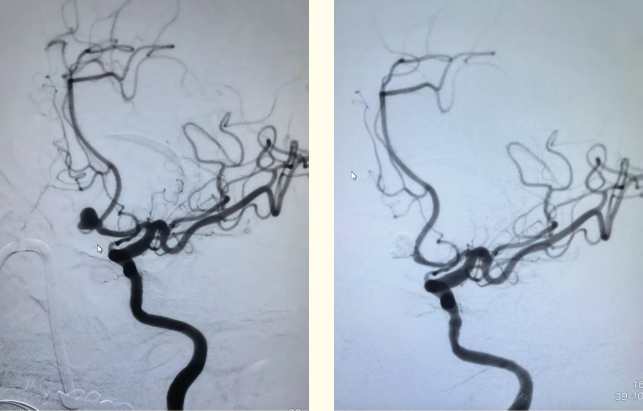

▲近期患者乙术前、术后颅脑DSA影像。

脑动脉瘤一旦破裂出血,死亡率致残率非常高,能够迅速且有效地进行微创治疗是神经外科医师一致追求的目标。2025年,即墨区中医医院选派杨为卓到复旦大学附属华山医院进修学习出血和缺血性脑血管病的综合介入治疗。杨为卓学成回到即墨区中医医院后,通过多学科合作,已开展脑动脉瘤破裂出血介入栓塞5例,大血管闭塞取栓3例,脑动脉重度狭窄球囊扩张成形支架置入1例。以上病例多为高龄危重患者,标志着医院在脑血管病介入治疗方面迈上了一个新台阶,为广大脑血管病患者提供了更多更好的治疗选择,为患者筑起更加牢固的生命防线。